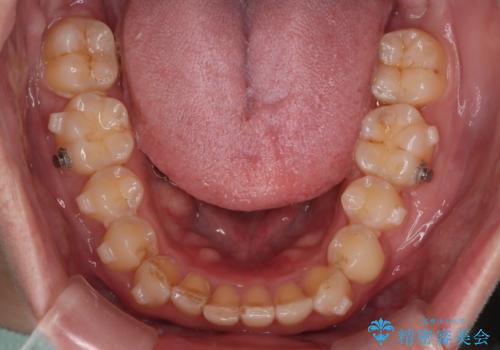

- インビザライン・ワイヤー装置(クリア装置)

右側臼歯部の咬合改善のために、臼歯部のみ部分的なワイヤー矯正を行い、咬合改善がみられてからインビザラインにて全体的な矯正を行なっていく治療計画を立てました。

噛み合わせをよくするために、ワイヤー矯正とインビザライン矯正のどちらの期間も必要な箇所にゴム掛けを行いながら治療を行いました。